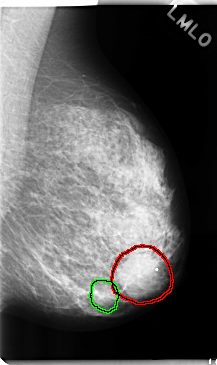

FILE: C_0248_1.LEFT_MLO.OVERLAY

TOTAL_ABNORMALITIES 2

ABNORMALITY 1

LESION_TYPE MASS SHAPE ROUND MARGINS CIRCUMSCRIBED

ASSESSMENT 4

SUBTLETY 5

PATHOLOGY BENIGN

TOTAL_OUTLINES 1

BOUNDARY

ABNORMALITY 2

SUBTLETY 3